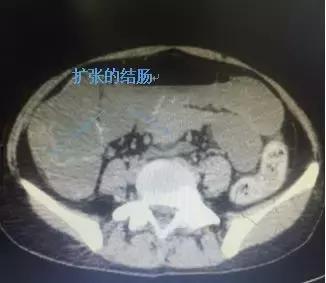

患者金某,排便困难数十年,长期保守治疗效果不佳,今年2月患者因“停止排便1月伴腹痛、腹胀1天”慕名来我院肛肠外科就诊。急诊CT检查发现结肠内大量干硬粪便、结肠重度扩张,导致小肠也扩张。入院诊断“慢性结肠传输障碍行便秘(Slow Transit constipation——STC)、结肠梗阻”。

分析病情,患者结肠随时有破裂的风险,危及患者生命,并且患者长期饮食差,又伴有腹痛、呕吐,导致营养状态欠佳,水电解质紊乱。术前评估不能耐受次全大肠切除术,肛肠外科运用控制性损伤原理,急症行“乙状结肠切开取粪石、肠减压并肠造瘘术”。术中发现结肠扩张,部分肠壁菲薄,排出粪石约4千克。术后给予纠正水电解质紊乱、营养支持等治疗,好转出院,3月后患者营养状态改善后再次入院,行腹腔镜下次全结肠切除术。由于围手术精细规划,快速康复理念贯穿始终,术后1周患者康复出院。